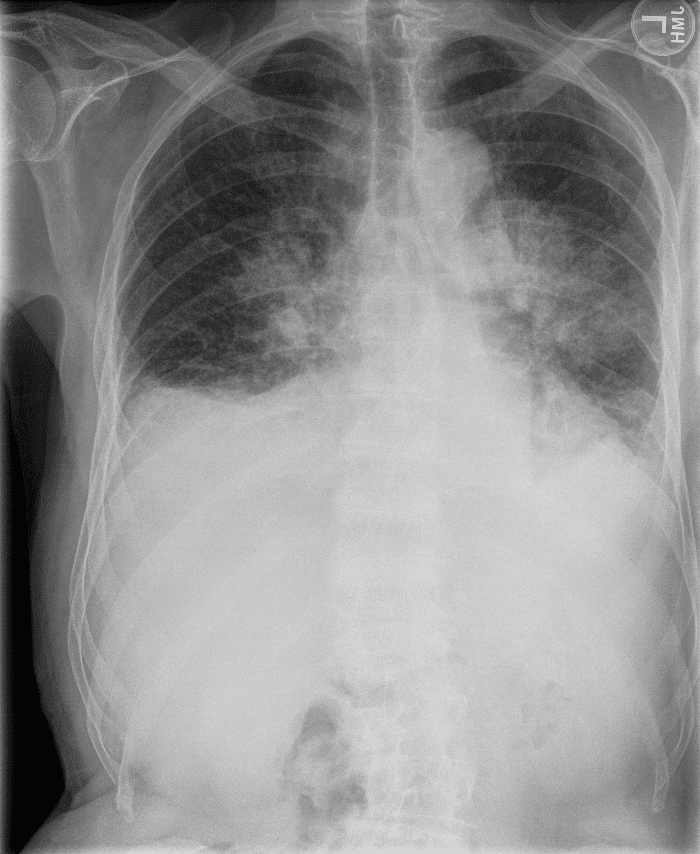

Practice Cases